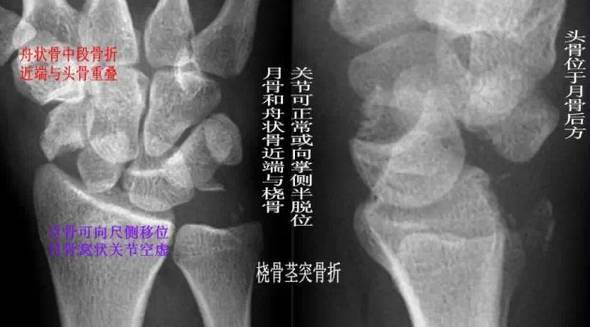

(2) 经舟骨月骨脱位:除月骨脱位外,同时伴有舟骨骨折,且骨折近段随月骨一起向前脱位,骨折远段仍处于原位置。

经舟骨月骨脱位影像特点

(4)经舟骨月骨周围脱位:表现为月骨周围脱位伴舟骨骨折,且骨折远段随头骨向后脱位,而骨折近段与桡骨、月骨关系保持正常。

经舟骨月骨周围脱位影像特点